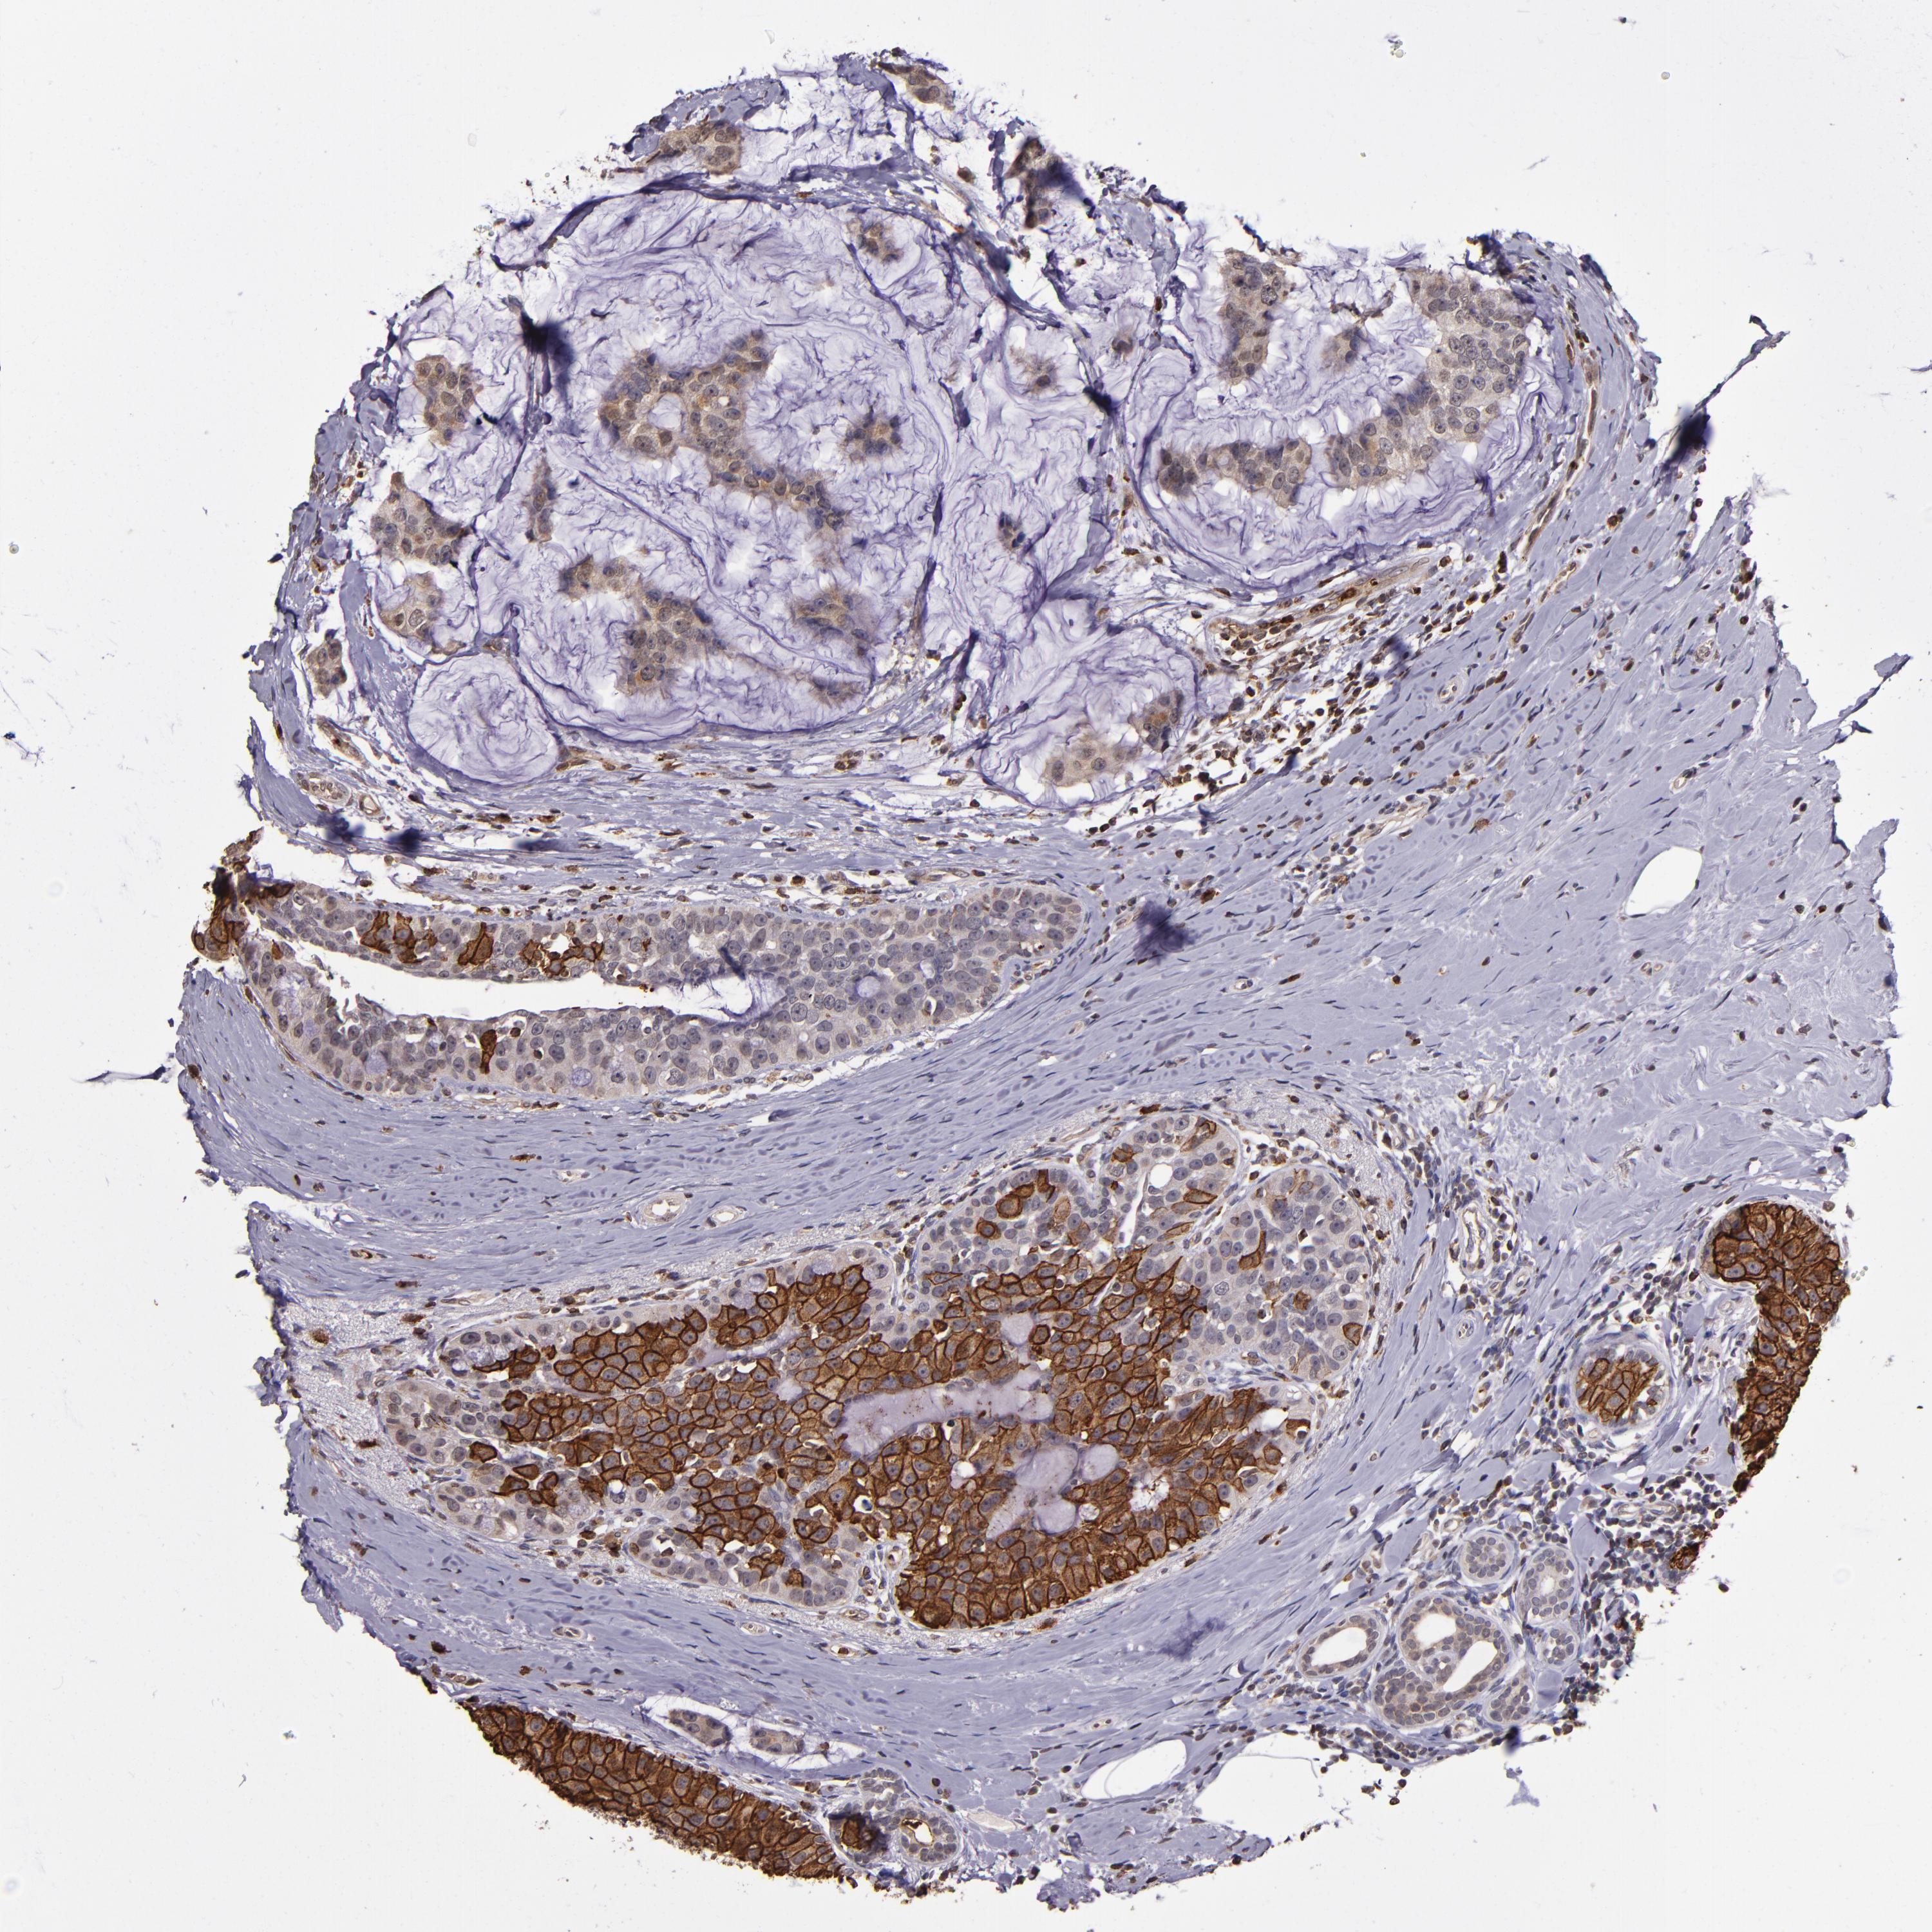

CANCER BREAST CANCER Show tissue menu

BRCA TCGA BRCA VALIDATION PROTEIN EXPRESSION

ANTIBODIES

AND

VALIDATION